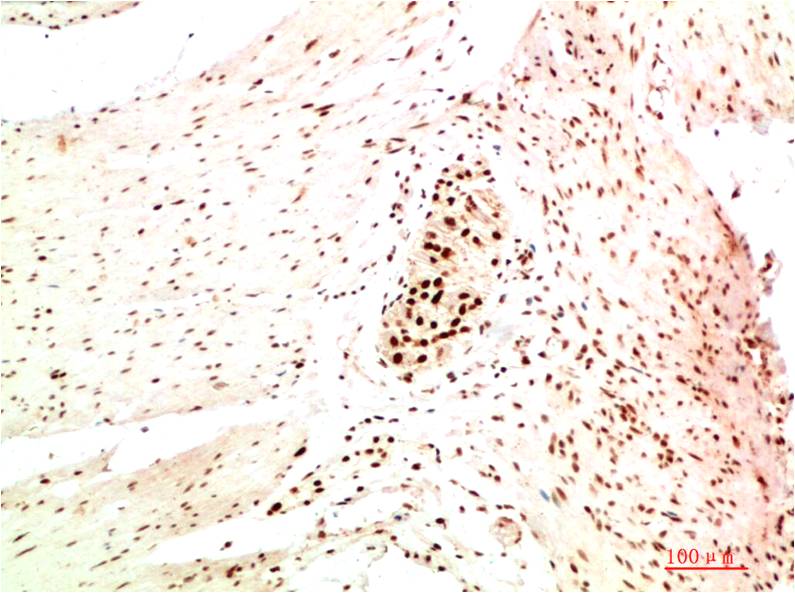

HP-1α Mouse Monoclonal Antibody(5E3)

Catalog NO.:BE3698

Applications :WB, IHC

Reactivity :H,R,M

Heterochromatin protein 1 (HP1) is a family of heterochromatic adaptor molecules involved in both gene silencing and higher order chromatin structure. All three HP1 family members (α, β, and γ) are primarily associated with centromeric heterochromatin.

Recommended dilutions: WB 1:500-1,000 IHC 1:200-500